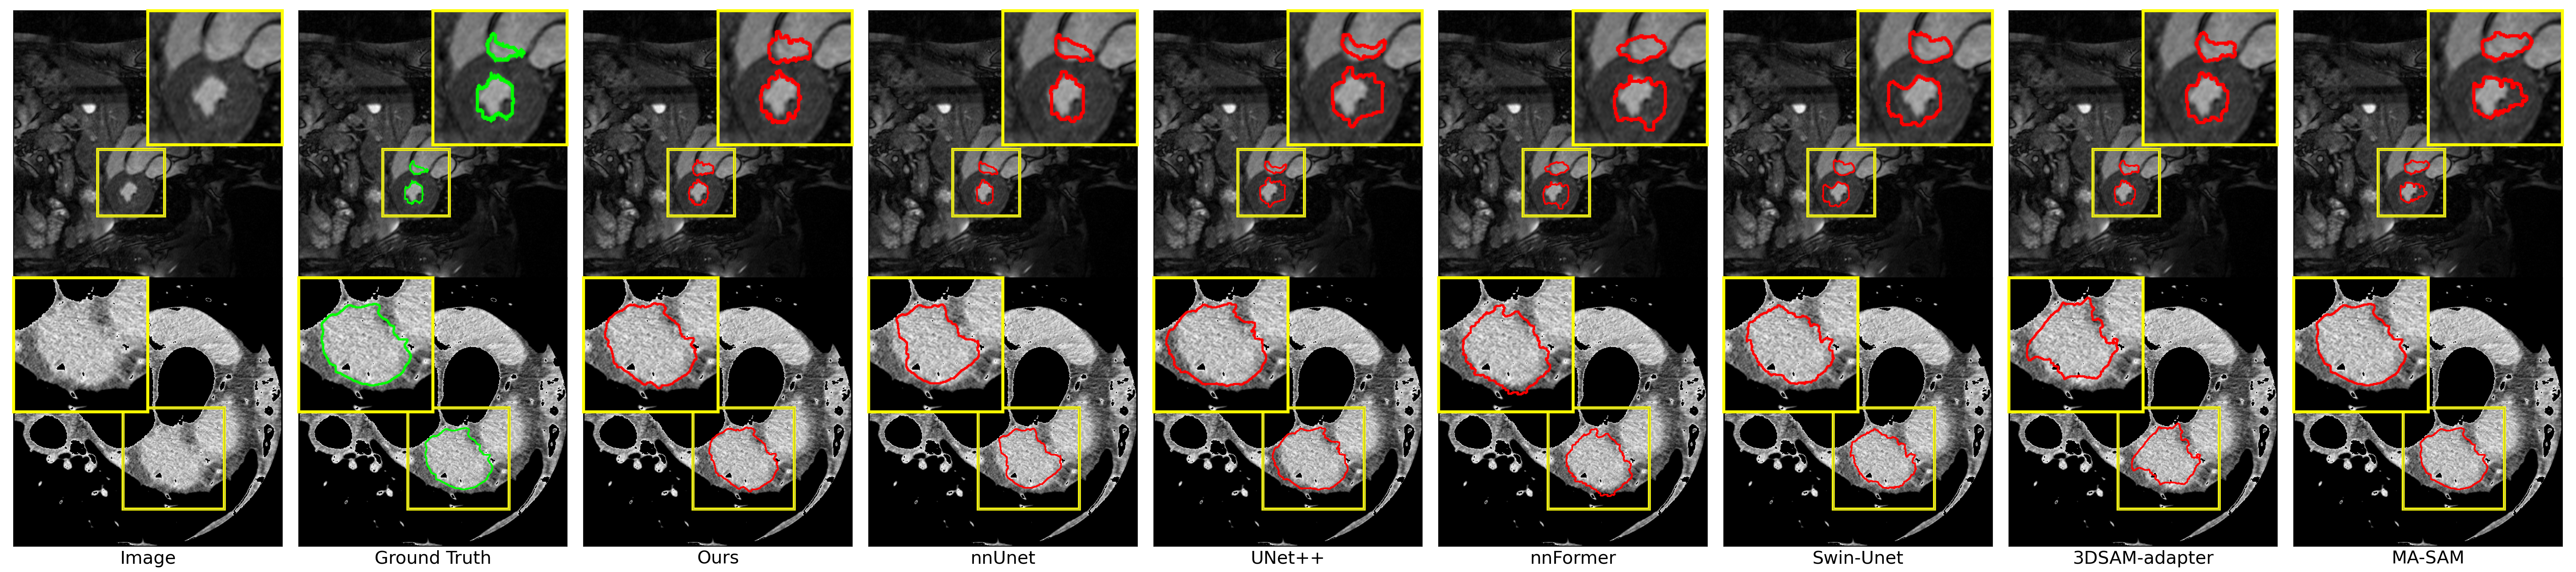

Refer to caption

Figure 5: Qualitative visualization of segmentation results generated from different methods for MRI cardical tumor segmentation

In addition, in the context of cardiac tumor segmentation using MRI, as shown in Figure 5, a qualitative assessment of predicted masks from various segmentation models indicates that our AutoSAM Adapter produces visually superior results, especially in terms of boundary precision, when compared to existing SOTA methods.